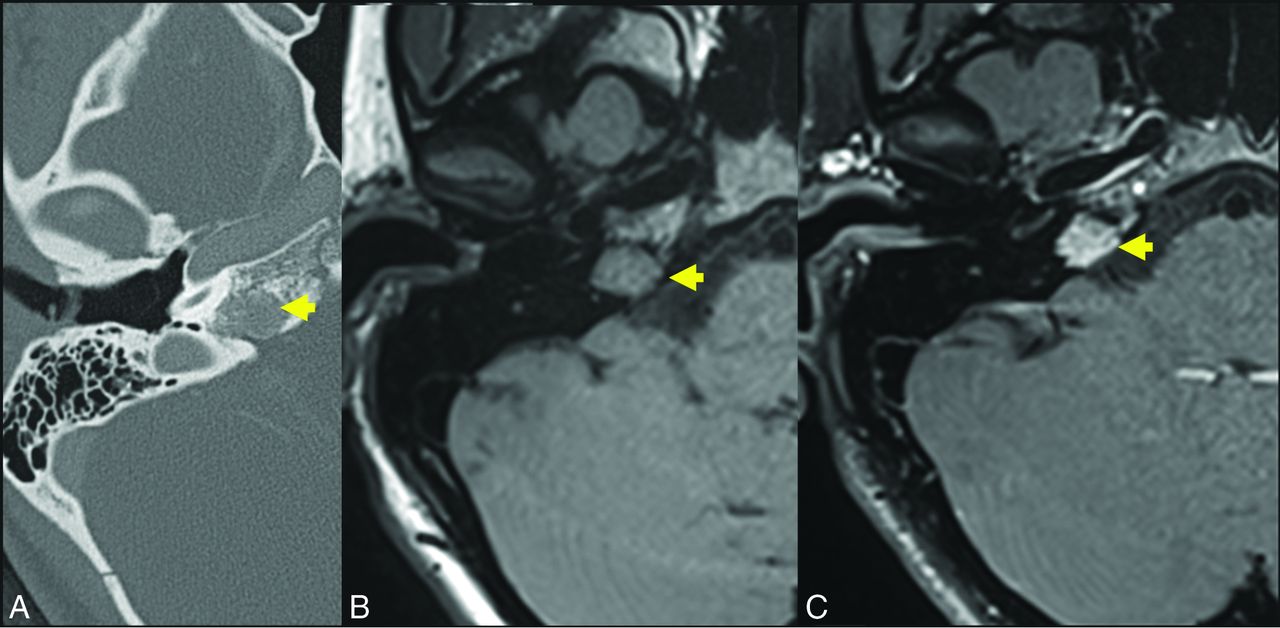

A 57-year-old woman who presented with right facial synkinesis. Noncontrast T1WI (A) and contrast-enhanced T1WI (B) demonstrate an enhancing lesion centered at the level of the right FN hiatus (yellow arrow, A and B), with corresponding increased signal on T2WI (C, yellow arrow indicates lesion). Differential considerations included both schwannoma and IOVM of the FN. Axial (D) thin-section CT of the temporal bone demonstrates an expansile, lucent lesion at the level of the anterior genu of the FN and FN hiatus (yellow arrow, D). The internal trabeculae help to confirm the diagnosis of IOVM because schwannoma would be less likely to show internal calcification. The diagnosis of IOVM was confirmed on pathology.

The location for an IOVM is characteristically at the geniculate portion of the FN, which is not surprising given its rich venous and capillary plexus. There is a rarer occurrence elsewhere along the FN, namely at the internal auditory canal or second genu.39 FN IOVMs often infiltrate beyond the margins of the FN canal and geniculate ganglion, aiding in discrimination from facial nerve schwannoma.

CT typically reveals an expansile lesion with irregular margins centered at the geniculate fossa, demonstrating characteristic internal bony spicules or trabeculae, a honeycomb pattern, or small, needle-shaped calcifications as recently described by Yue et al.40 However, when small, an FN IOVM may fail to show typical bony densities and only widen the FN canal. Discrimination may then prove difficult between an IOVM and neoplasm, most commonly a schwannoma in this location.41 MR imaging typically reveals a mass of T1-hypointense or -isointense and T2-hyperintense signal that may be heterogeneous depending on degree of bony matrix. Typically, an FN IOVM appears as a patchy or geographic focus of enhancement, whereas a schwannoma may appear ovoid or tubular. Particularly when lesions are small, differentiation may be very difficult, and ultimately both CT and MR imaging are frequently required in this differential diagnosis.